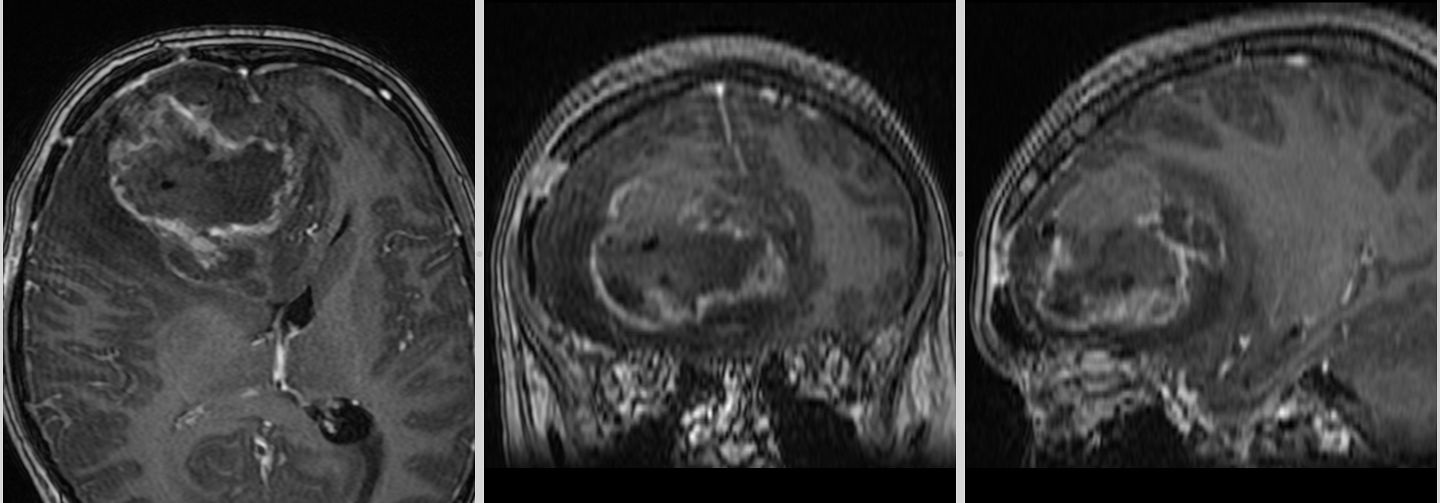

Totuși, la aproximativ 3 ani de la intervenția inițială, RMN-ul cerebral a evidențiat o modificare suspectă la nivelul zonei operate.

Aspectul nu era cel clasic de recidivă agresivă.

Leziunea avea caracteristici mai apropiate de un proces de tip low-grade, cu evoluție lentă și fără semne de agresivitate marcată.

Spectroscopia RMN a confirmat o progresie tumorală de tip low-grade, cu peak de colină (Cho) și N-acetil-aspartat (NAA).

În acest context, s-a decis reluarea tratamentului cu Temozolomidă.